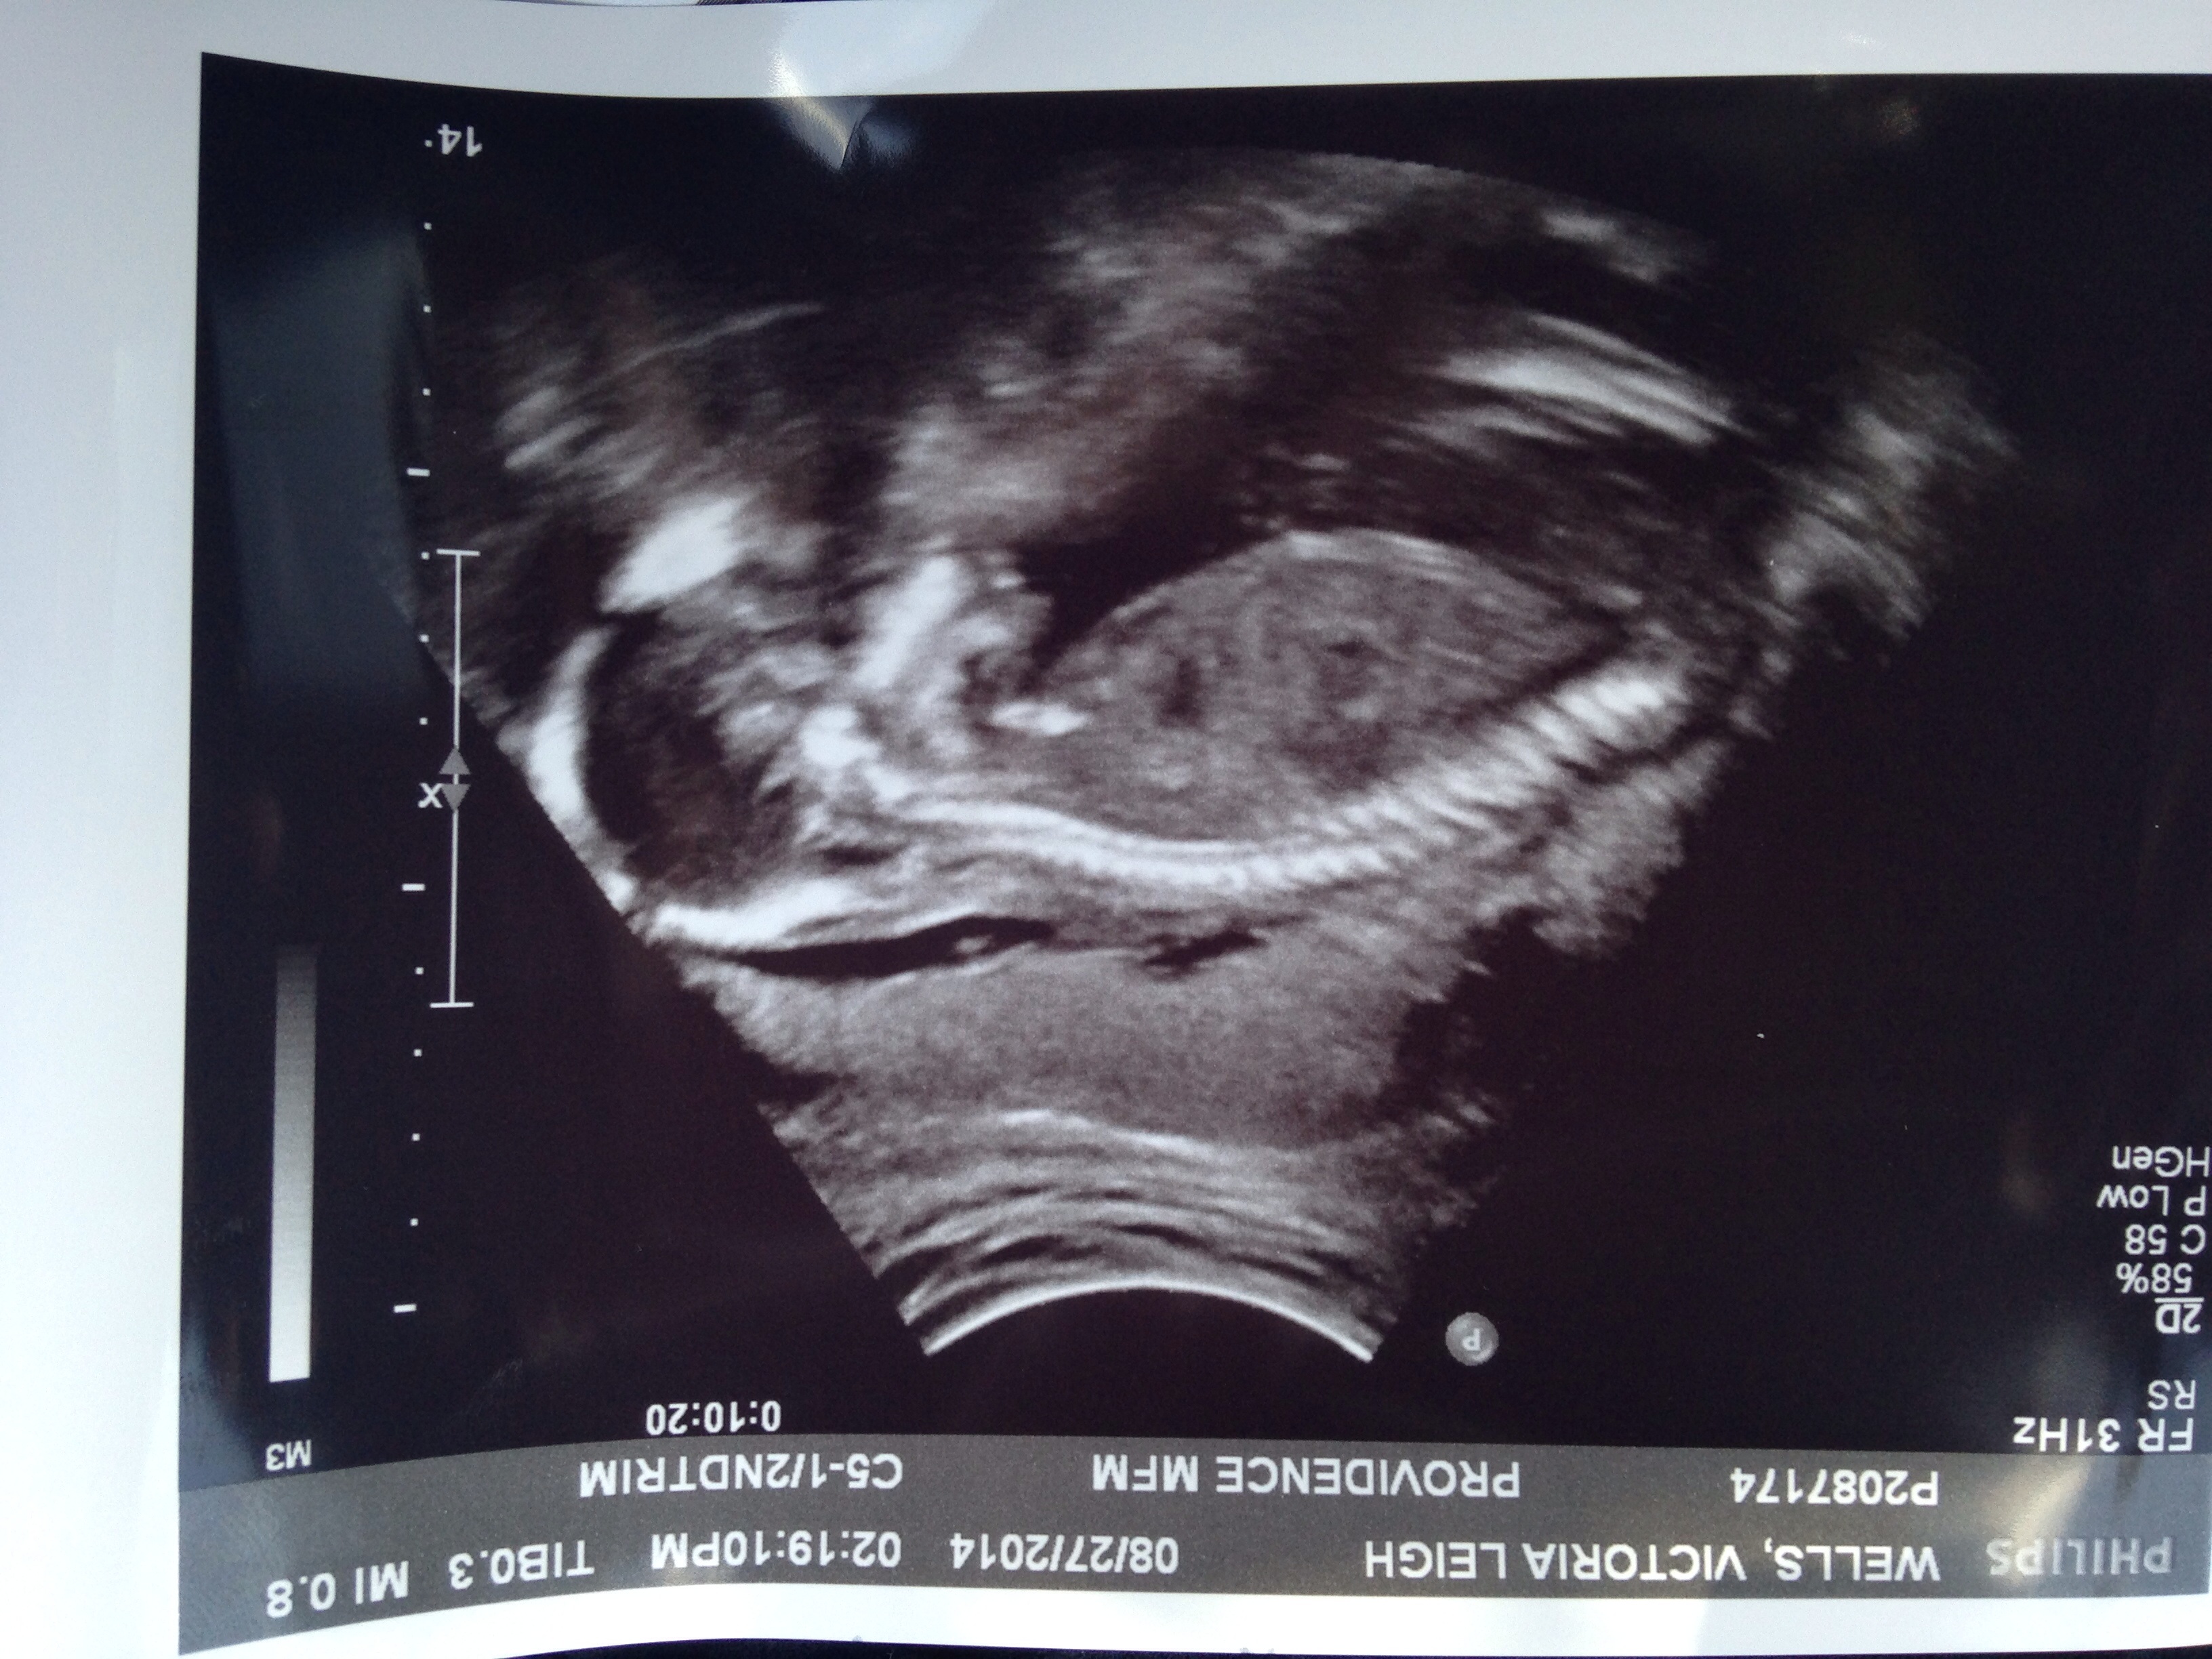

1st u/s pic at about 13w

2nd at 21w. Team blue! (Again!)